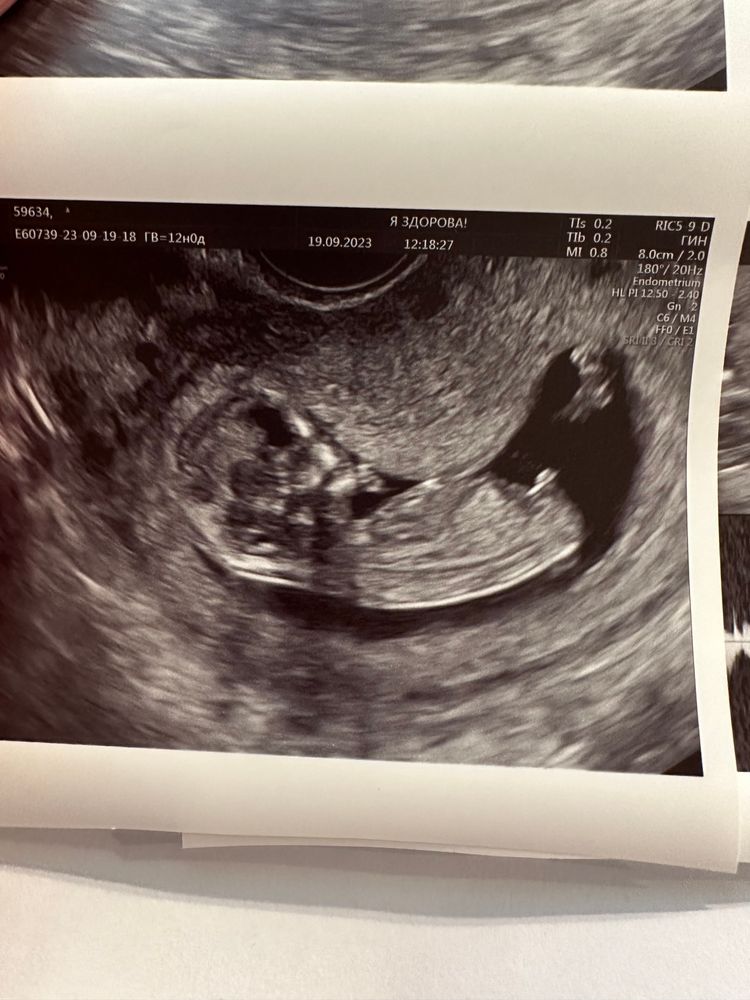

Видела много постов,где по фото писали пол😁можно и я теперь побалуюсь)

могу ошибаться, но кажется мальчишка. На первом снимке вижу стручок вроде как вверх направлен.

Мальчик 100% у меня девочка, положение вообще другое) при чем трижды)))